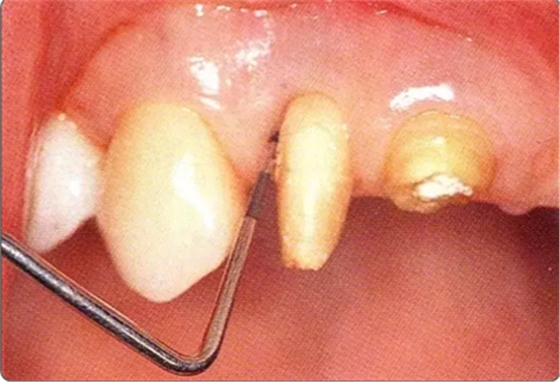

圖10-1

遠中部有8mm的牙周袋。上頜前牙部等需要考慮審美性的部位進行GTR法,但也可能會出現(xiàn)齦瓣壞死導致牙齦乳頭喪失,反而導致審美性變差的情況。